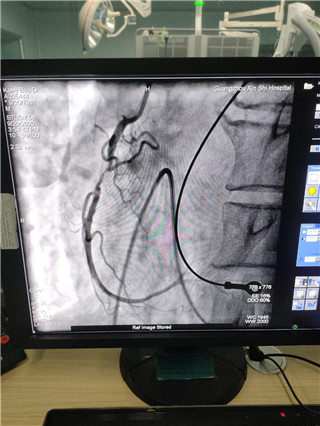

急诊冠脉造影显示:抗栓治疗后血管再通,右冠2段近端与左前降支近端均残余狭窄98%;在内一科邓鹤秋主任的带领下,分别对两条犯罪血管成功实施了直接PCI术,各植入药物洗脱支架一枚,前向血流恢复TIMI 3级,结果非常满意。经术后CCU的进一步救治,目前患者血清酶学指标已基本恢复正常,无需血管活性药物已能维持血流动学稳定,生命体征平稳,已于病房内活动接受心脏康复治疗。